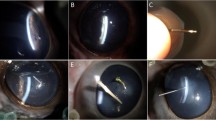

In ex vivo imaging, 3D-UBS and CT both identified metal and glass with high contrast. Figure 11 shows that the contrasts of both materials with CT were high, as their linear X-ray attenuation coefficients are high. The presence of highly attenuating materials i.e., glass, metal cause CT artifacts (i.e., photon starvation), resulting in a dark region around the IOFBs. This coupled with high HU values of the materials provides high CNR for metal or glass IOFBs. However, the effect in terms of IOFB detection was minimal, as 3D-UBS also provides good contrast. We observed acoustic shadowing for metal, and reverberation artifacts for glass IOFBs in 3D-UBS. Although the presence of such artifacts can help detect IOFBs, they prevent accurate measurements of the size of the foreign body.

In ex vivo imaging, 3D-UBS and CT both identified metal and glass with high contrast. Figure 11 shows that the contrasts of both materials with CT were high, as their linear X-ray attenuation coefficients are high. The presence of highly attenuating materials i.e., glass, metal cause CT artifacts (i.e., photon starvation), resulting in a dark region around the IOFBs. This coupled with high HU values of the materials provides high CNR for metal or glass IOFBs. However, the effect in terms of IOFB detection was minimal, as 3D-UBS also provides good contrast. We observed acoustic shadowing for metal, and reverberation artifacts for glass IOFBs in 3D-UBS. Although the presence of such artifacts can help detect IOFBs, they prevent accurate measurements of the size of the foreign body.